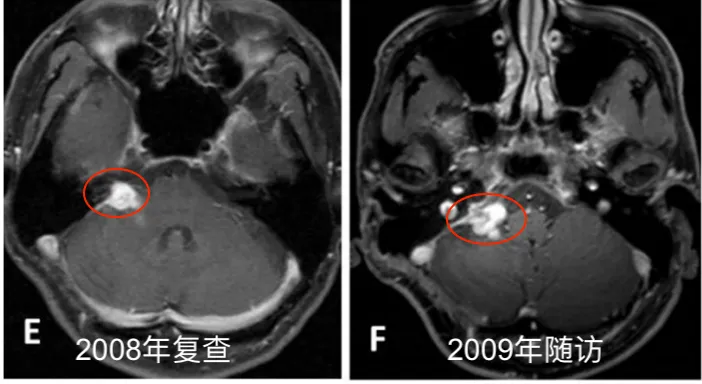

此后,他坚持每六个月复查一次。影像资料(图1 E-J)记录了数年间的随访情况。